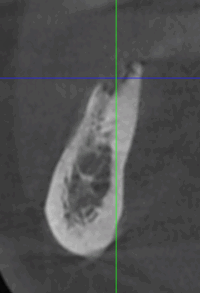

Reprise de traitement implantaire

La reprise de traitement désigne le processus par lequel un patient reprend des soins après un échec de traitement implantaire ou lorsque des complications surviennent. Voici les étapes typiques d’une reprise :

En cas d’échec ou de complications, la reprise de traitement implique une évaluation diagnostique, une extraction (si nécessaire), une cicatrisation, puis une reconstruction osseuse suivie d’une nouvelle implantation.